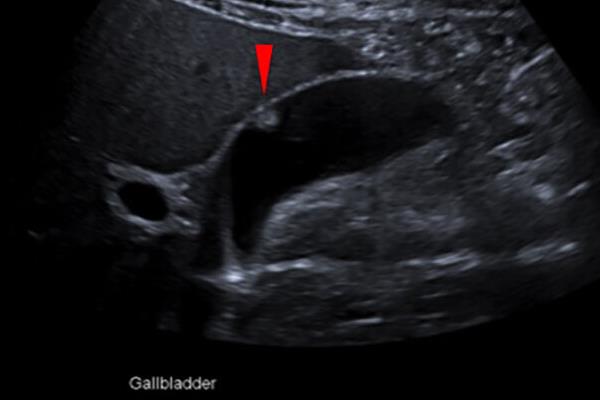

پولیپهای کیسه صفرا زائدههایی هستند که از دیواره داخلی کیسه صفرا بیرون میآ ...

اگر اخیراً متوجه وجود پولیپ کیسه صفرا در بدن خود شدهاید، شاید این سؤال برایتان پیش آمده باشد که آیا این پولیپ خطرناک است؟ در این مقاله، درباره پولیپهای کیسه صفرا، روشهای شناسایی از طریق سونوگرافی، علائم، خطرات و گزینههای درمانی صحبت میکنیم.

پولیپهای کیسه صفرا زائدههایی هستند که از دیواره داخلی کیسه صفرا بیرون میآیند. در بسیاری از موارد، این پولیپها خوشخیم و بیخطر هستند، به این معنا که سرطانی نیستند. حدود ۹۵٪ از پولیپهای کیسه صفرا غیرسرطانی هستند و معمولاً در حین سونوگرافیهای روتین شکم یا بررسیهایی که برای سایر دلایل انجام میشوند، کشف میشوند.

بیشتر پولیپهای کیسه صفرا بهندرت سرطانی میشوند، اما اندازه پولیپ میتواند در تعیین خوشخیم یا بدخیم بودن آن مؤثر باشد. بهطور کلی، سونوگرافی پولیپ یکی از راههای اولیه برای تشخیص اندازه و خطرات احتمالی پولیپها است:

پولیپهای کوچک (کمتر از ۱۰ میلیمتر): پولیپهایی که اندازهشان کمتر از ۱۰ میلیمتر باشد، به احتمال زیاد سرطانی نیستند و معمولاً نیازی به درمان ندارند. با این حال، توصیه میشود سونوگرافیهای دورهای برای بررسی تغییرات احتمالی انجام شود.

پولیپهای بزرگتر از ۱۰ میلیمتر: پولیپهایی با اندازه بیش از ۱۰ میلیمتر میتوانند خطر سرطانی شدن داشته باشند. برای این نوع پولیپها، سونوگرافی منظم پولیپ و در صورت نیاز کولهسیستکتومی (برداشتن کیسه صفرا) توصیه میشود تا از خطرات جلوگیری شود.